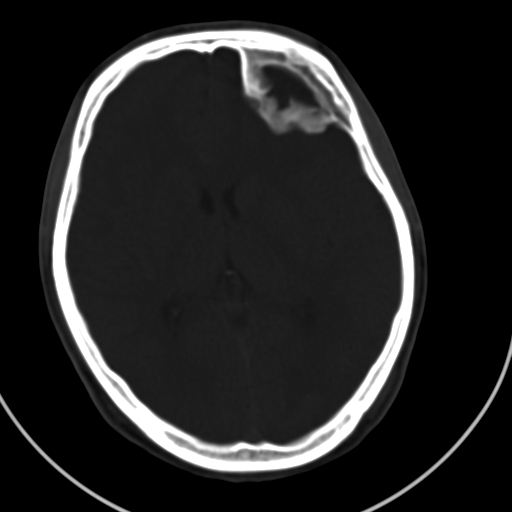

标题: CT21939:男20岁,外伤一年后,现头疼. [打印本页]

标题: CT21939:男20岁,外伤一年后,现头疼.

颅骨凹陷性骨折并压迫脑组织致大脑镰下疝!

是硬膜外血肿机化还是陈旧性凹陷性骨折?

硬膜外血肿机化

结合文献报道,考虑血肿继发改变,血肿骨化?

如果是骨折,外板正常内板这么明显凹陷,请问这样的骨折是怎样形成的?形成的机理是什么?有没有可能形成?

硬膜外血肿伴包膜钙化

左侧额部硬膜外血肿机化、骨化。

左侧额部硬膜外血肿机化、骨化